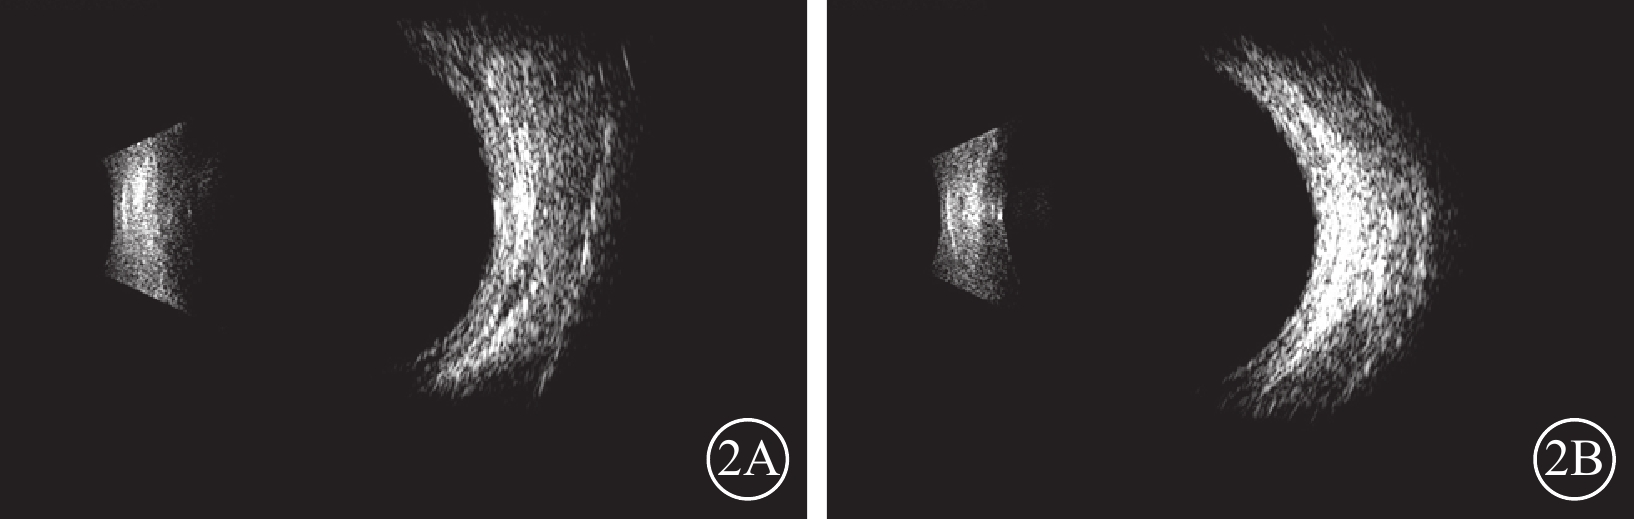

圖2

吲達帕胺致雙眼葡萄膜滲漏綜合征患者雙眼超聲像 2A示右眼,周邊球壁增厚;2B示左眼,周邊球壁略增厚